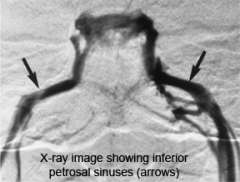

Inferior petrosal sinus sampling

X-ray of Inferior Petrosal Sinus Sampling

In some cases, MRI fails to identify an abnormality. If your doctor suspects Cushing's disease, he or she may order super-selective inferior petrosal sinus sampling (IPSS).

IPSS must be performed by an experienced interventional neuroradiologist because it carries risk, and if done inappropriately, can give misleading results.

The inferior petrosal sinuses are veins that occur on both sides of the pituitary gland.

• Blood leaving the right half of the pituitary gland drains into the right inferior petrosal sinus and vice versa.

• Specially trained interventional neuroradiologists can thread a tiny catheter into the inferior petrosal sinus. Blood samples are then taken from each sinus and from a vein just below the heart.

If the ACTH level is the same in the inferior petrosal sinus compared to the vein below the heart, this suggests that a tumor somewhere else in the body (ectopic, not pituitary) is producing ACTH.

In Cushing's disease, the ACTH level in the inferior petrosal sinus is much higher compared to the vein below the heart